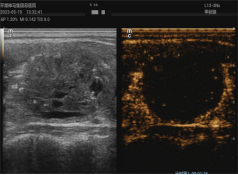

1、超聲引導(dǎo)下腫瘤的熱消融治療

熱消融技術(shù)是指在超聲實(shí)時引導(dǎo)下,將消融針插入病灶內(nèi),產(chǎn)生的高溫在短時間內(nèi)使病灶組織凝固壞死的方法。這一方法操作微創(chuàng)精準(zhǔn),效率高,范圍可控,不良反應(yīng)小,可重復(fù)性強(qiáng),實(shí)現(xiàn)了治療的微創(chuàng)、美觀、有效、安全的完美結(jié)合。科室開展甲狀腺、乳腺、肝臟、子宮、淋巴結(jié)等多臟器實(shí)體腫瘤的熱消融治療多年,積累了豐富的臨床診治經(jīng)驗(yàn),患者受益,提高了患者的生活質(zhì)量。